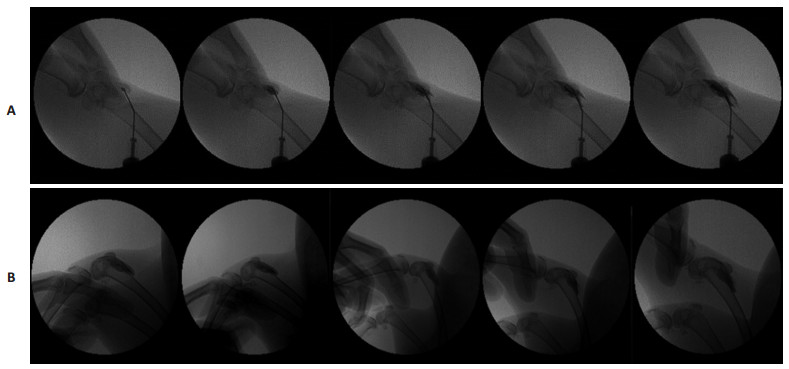

2.4 HA示踪模型的动态X线透视观察结果X线透视的动态摄像结果显示:以0.5 mL 5%碘海醇示踪的HA-I制剂可清楚显示HA药物进入关节腔,并向周围扩散和再分布的过程(图 5A)。膝关节屈伸运动后,髌骨下方给药的HA仍然主要存在于髌骨下方,仅少部分向四周扩散(图 5B)。而关节线给药的HA(图 6A),则主要向后关节腔转移(图 6B)。可见,本研究的药物示踪模型可有效甄别不同给药位点给药后HA在动物膝关节腔内分布特点的差异,示踪效果肯定。

图 5 X线透视下兔膝关节腔髌骨下给药的HA动态观察 Figure 5 Dynamic observation of HA administered through the patella medial approach by X-ray. A: Static; B: Knee movement. |

图 6 X线透视下兔膝关节腔关节线给药的HA分布动态观察 Figure 6 Dynamic observation of HA administered through the medial joint line approach by X-ray. A: Static; B: Knee movement. |